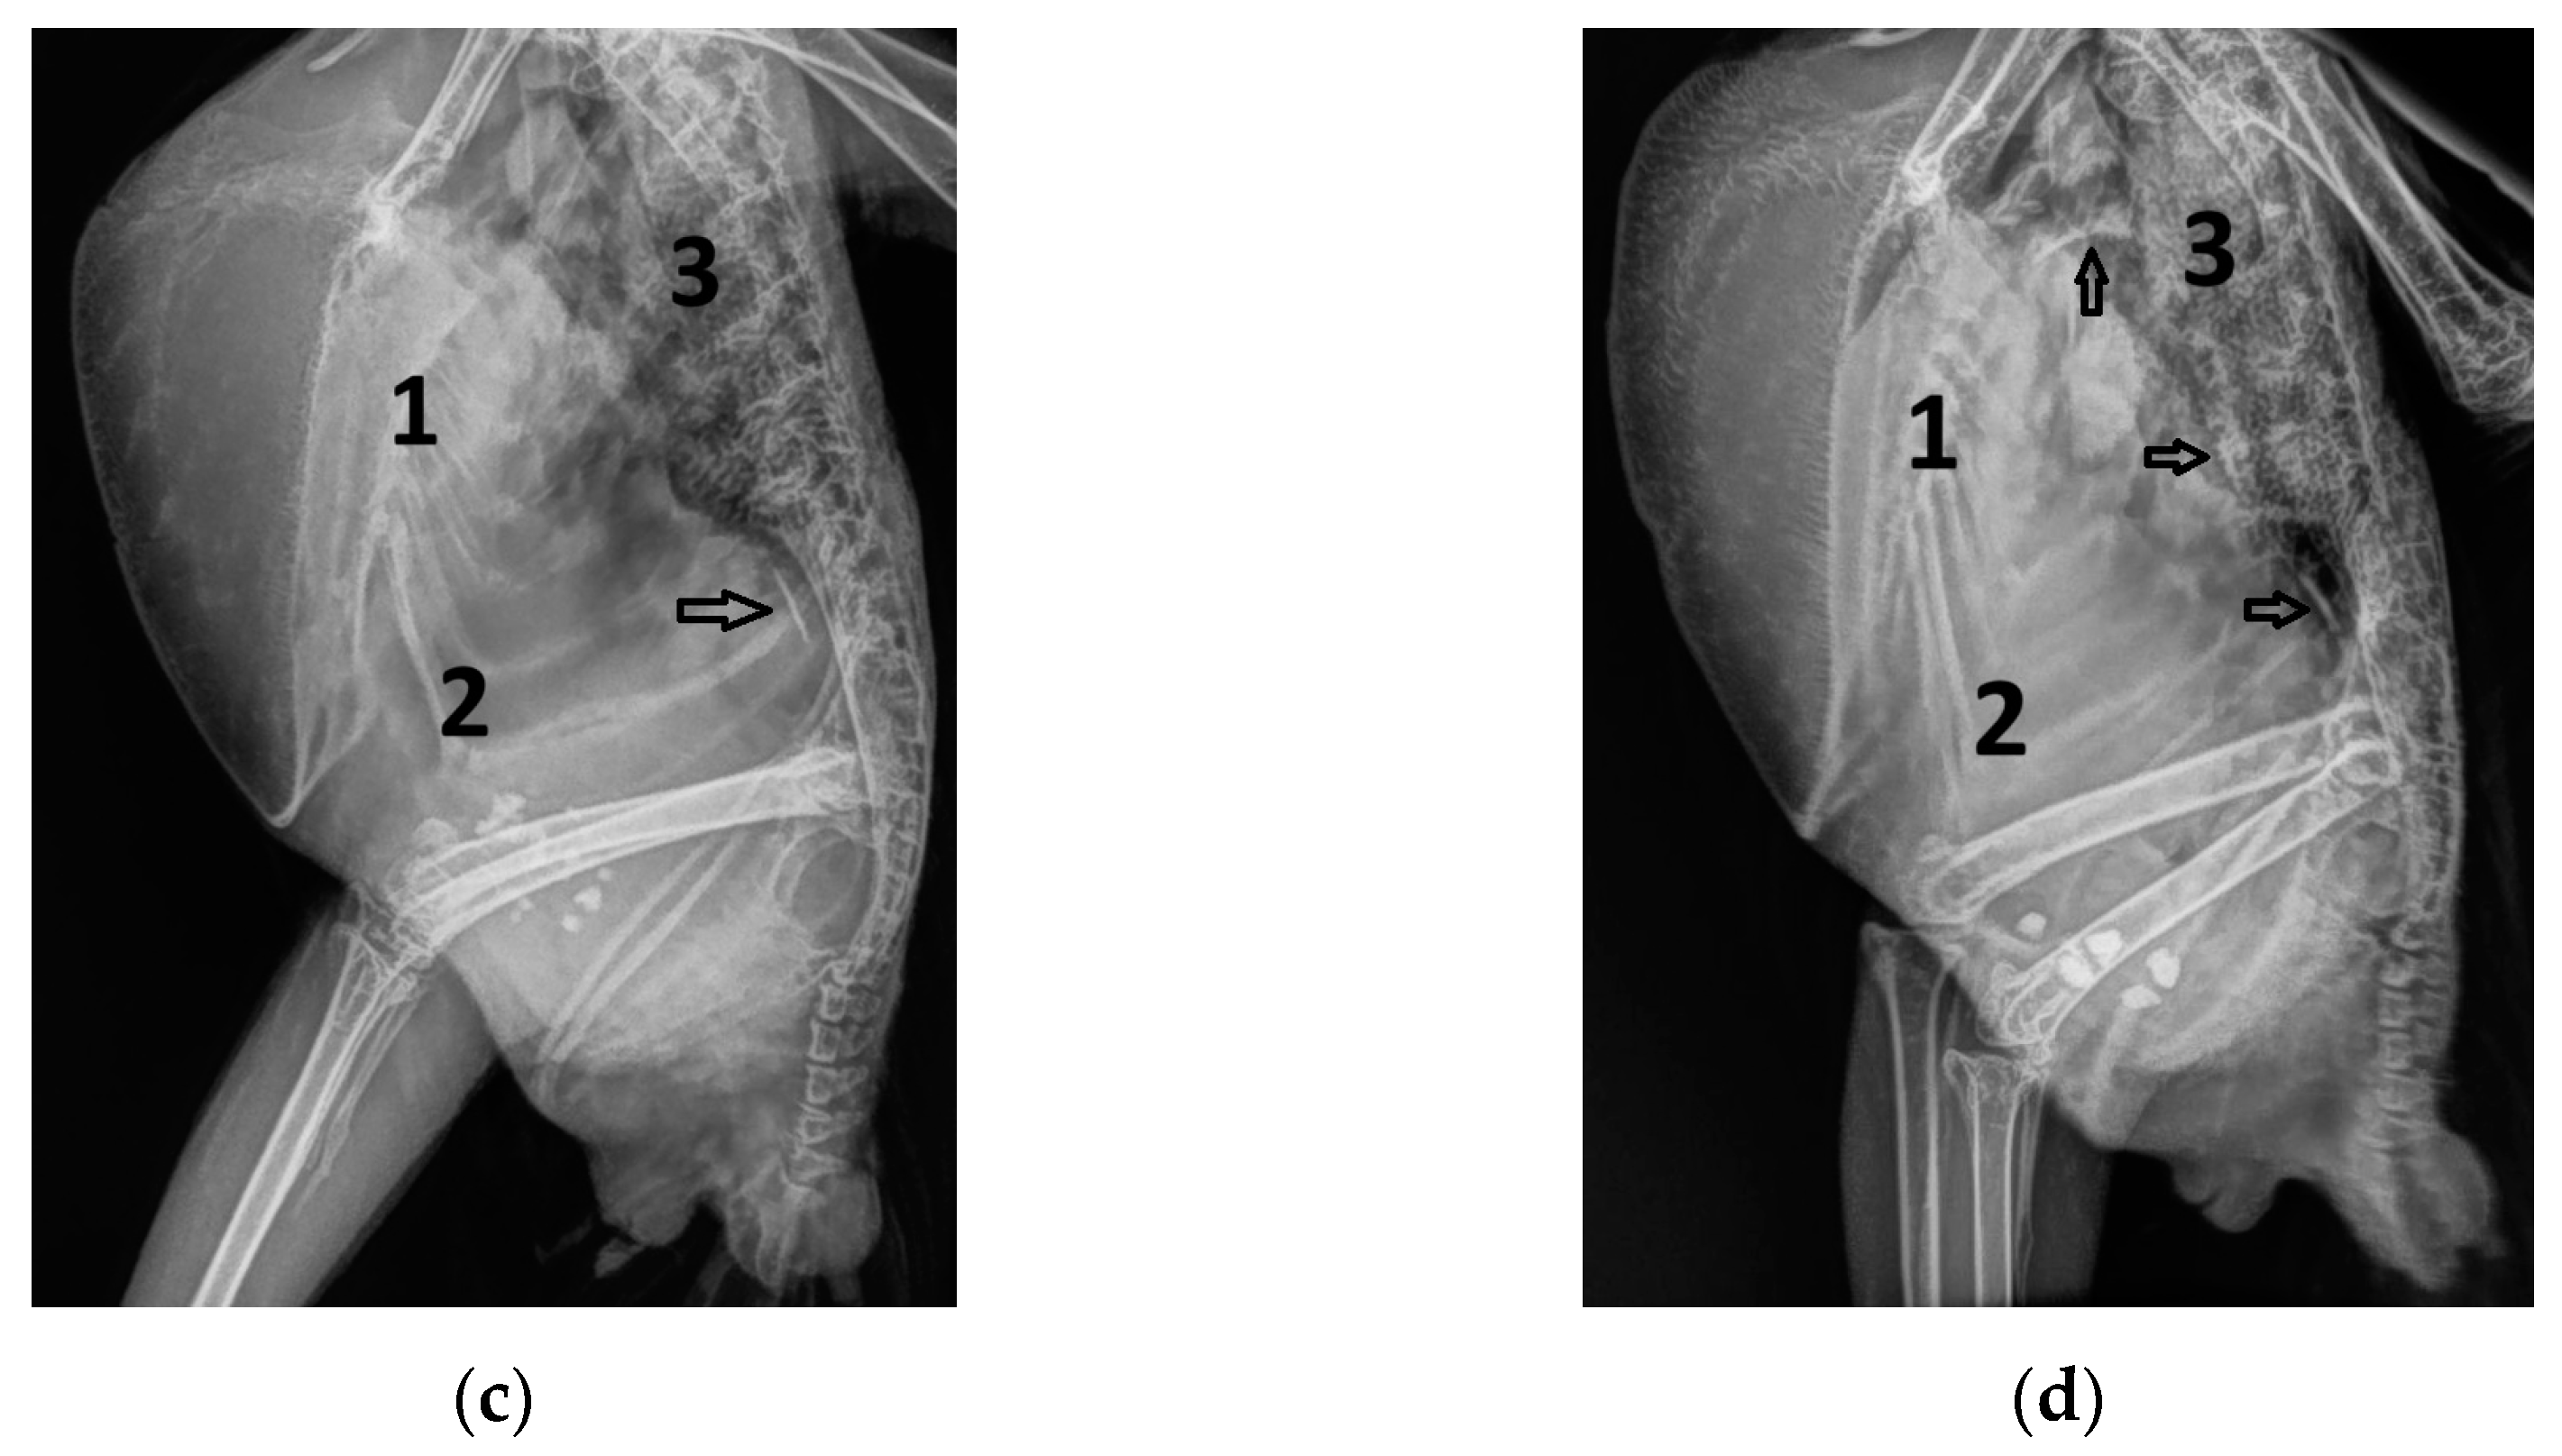

3. Results

3.1. Shape of PAFP and AOFP of Grey Parrots

3.2. The Influence of Heart Failure on the Shape of the PAFP and AOFP

3.3. Influence of the Heart Rate on the Pulmonary and Aortic Blood Flow Profiles of the GPs